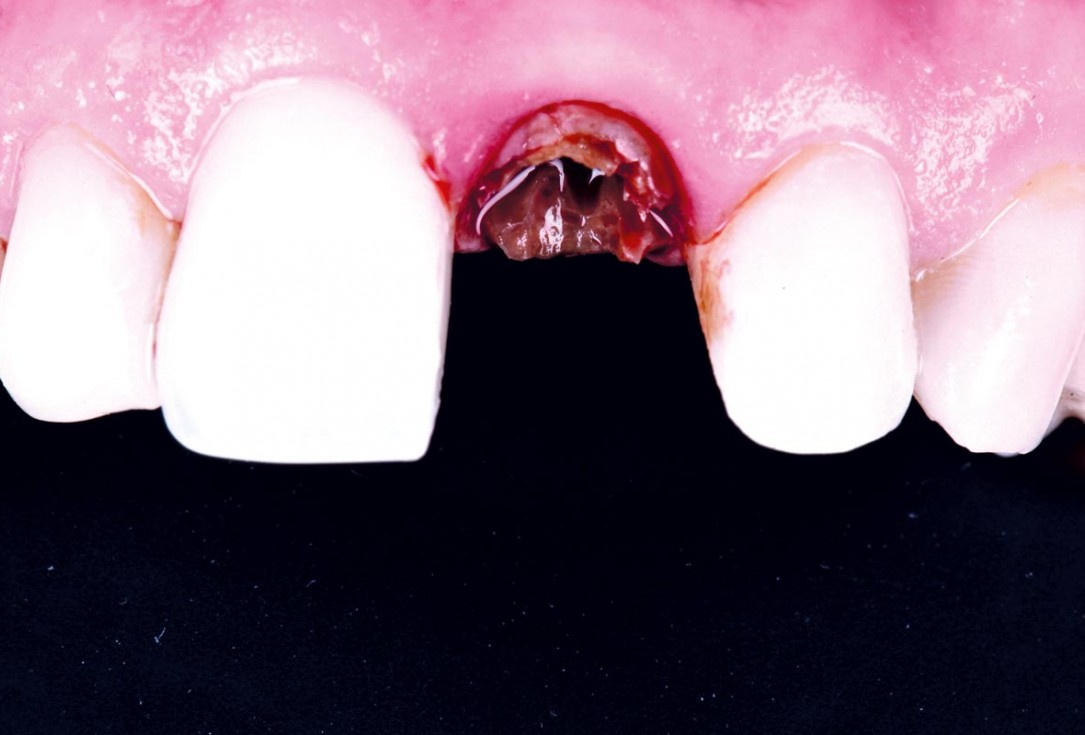

Immediate implant placement using cerabone® and collagen fleece - Dr. D. Jelušić

Pre-operative situation showing tooth 21 with deep periodontal pocket. Tooth presented with mobility grade III.